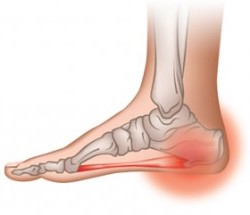

Пяточная шпора (плантарный фасциит) – выглядит как костные наросты в виде шпоры или шипа на подошвенной части стопы. При передвижении шип давит на окружающие ткани провоцируя развитие болевого синдрома. В среднем размеры шпоры обычно составляют 0,5-1,2 см. В медицине такой нарост называют – экзостоз.

Первым признаком болезни является сильная боль в области пятки. Чаще всего она усиливается при опоре на ногу утром после сна. Ее еще называют «стартовой болью». После в течение нескольких часов она немного притупляется, а к вечеру возникает с новой силой. Обычно место возникновения боли начинается с внутренней стороны пяточной области и распространяется по всей поверхности подошвы стопы. Еще одним симптомом является грубая и покрасневшая кожа в зоне нароста. Объясняется это тем, что шпора давит на мягкие ткани, вызывая тем самым воспаление. В редких случаях при попадании инфекции может возникнуть нагноение.